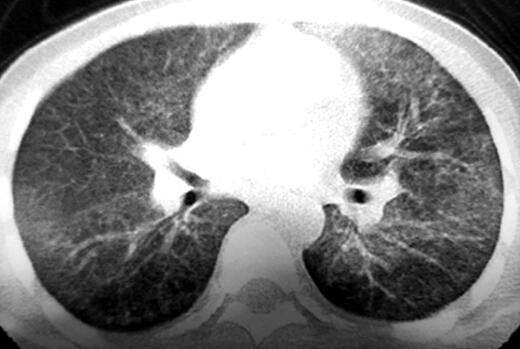

青年男性患者,农民,未婚,既往体健,否认呼吸系统疾病及其他慢性疾病史,无饲鸽、发霉物质接触史。1个月前受凉后出现发热,伴寒战,最高体温达40℃,呈稽留热,伴咳嗽、少许白痰,呼吸困难,活动后明显,无夜间憋醒,就诊于当地医院行胸部CT检查示:双肺对称的弥漫性分布的磨玻璃影(如图1、图2),予抗感染治疗,先后静脉滴注红霉素、头孢哌酮-舒巴坦半月余(具体用法用量不详),体温较前有所下降,但未降至正常,咳嗽、呼吸困难症状未见明显缓解,为求进一步诊治来诊。病来无胸痛、咯血,无腹痛、腹泻,无头痛,头晕,精神状态差,饮食睡眠差,二便可,近一月体重减轻约8kg。

图2

首次病史采集,按照常规问诊病史,但应注意以下细节详细询问协助明确诊断:患者既往体健,无呼吸系统疾病及其他慢性疾病史,此次发病主要症状为发热,伴有咳嗽、咳少许白痰、呼吸困难,按照常见病优先考虑原则应将呼吸道感染性疾病放在首位,但此次发病经过半个月的抗感染治疗,症状未见明显的缓解,那么原因有以下几种可能:①特殊的病原体感染,如结核、病毒及真菌等,普通抗生素治疗无效,可围绕以上特殊病原体感染的诱因、伴发症状进行询问;②先前使用的抗生素剂量不足,或者患者出现新的并发症如脓胸、脑炎等;③非感染性疾病,该患者病程中始终存在呼吸困难,气促、活动后加重,结合胸部CT示双肺对称的弥漫性分布的磨玻璃影,符合间质性肺疾病特点,考虑过敏性肺炎?淋巴细胞间质性肺炎?肺泡蛋白沉积症?在之后的查体、检查和治疗中,应该始终考虑以上几种原因,以更好的明确诊断。